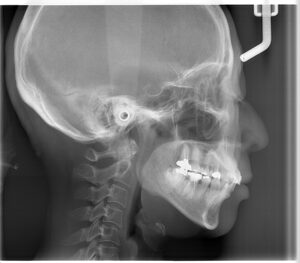

顎の関節の変形

初診時のレントゲンです。一番後ろの歯のさらに奥に親指のような形のようなものが見えます。これが顎の関節です。左右一対で対照的な形を本来はしています。向かって左は丸く普通の形をしていますが、右の顎の関節の形は左に比べて小さくなっています。左のかみ合わせの高さが低くなっていることで、下顎が右の奥に押し込まれています。そのことで顎の関節が年月をかけて変形していると考えられます。顎の関節が定位置にいられないことで顎の開閉口でカクっと鳴ったり、痛みを生じます。顎関節症の原因にはいろいろな原因が考えられていますが、かみ合わせが原因とされる顎関節症のメカニクスは述べた通りです。顎の関節の後ろには血管、神経が通っています。顎の関節が後ろに押し込まれることでその部分を圧迫してしまいます。その圧迫が片頭痛の原因になっていることもあります。ほうれい線もかみ合わせの高さが低くなっている方が深くなります。左右差が出るのはこういった理由です。かみ合わせ高さを含めて改善され、下顎が本来の位置に戻ることができれば、時間はかかりますが顎関節の形は年齢に関係なく戻っていくと報告されています。

頸椎の変化

少しわかりづらいですが、頸椎の角度が治療につれ少し立ってきています。まだ本来と逆の反り方ですが、それでも姿勢が矯正治療することで改善されていることがわかります。頭の重さは5㎏あります。その重さをバランス取って背骨の上に載せています。かみ合わせがズレていると前後左右のバランスが崩れます。舌の位置が後ろや下にあると呼吸しやすくするための姿勢にズらしています。いろいろなズレを修正するのに身体は不均衡な筋肉の使い方をします。その結果が口の周りだけでなく遠く離れたところまで不具合を生じさせてしまうのです。